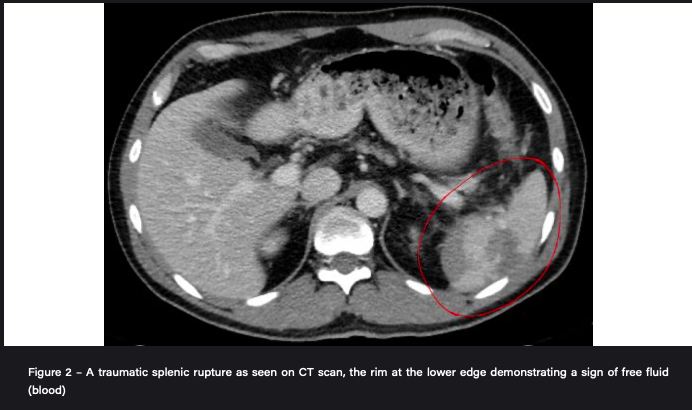

What investigations do you do for a suspected splenic rupture?

Haemodynamically unstable with peritonism: immediate laparotomy

Haemodynamically stable: urgent CT chest-abdomen-pelvis with IV contrast